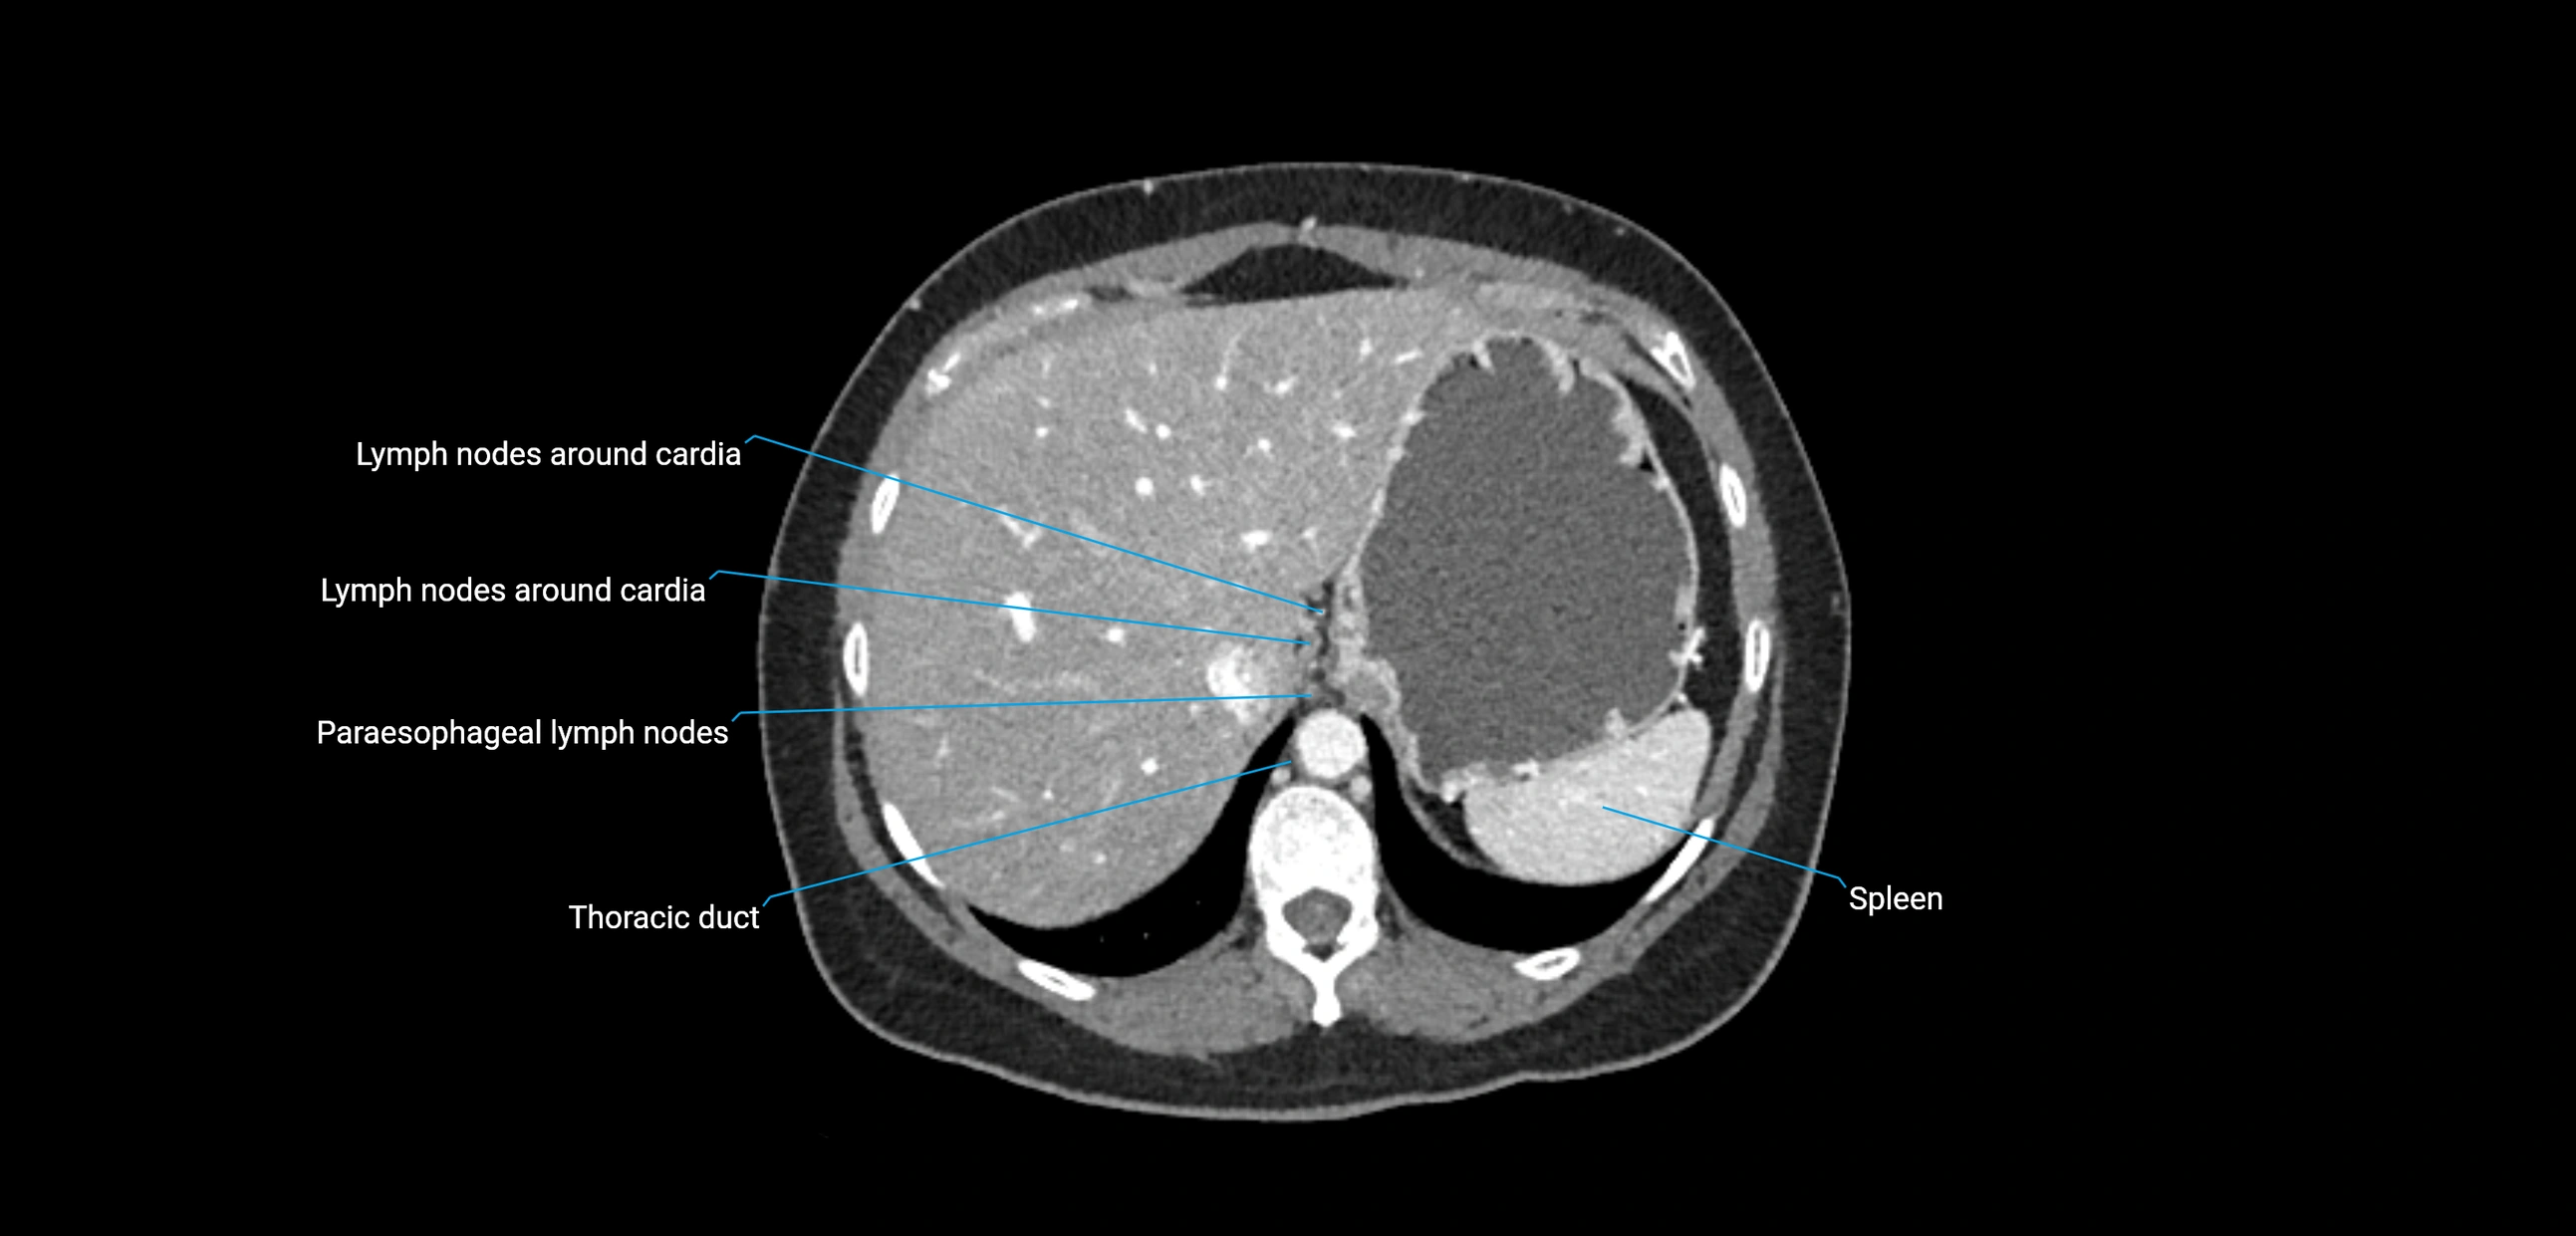

CT Appearance

CT Post-Contrast:

• Normal nodes enhance homogeneously

• Malignant nodes may show heterogeneous enhancement, central necrosis, or conglomerate formation

• Size >1 cm short axis is suspicious, though morphology and distribution are equally important